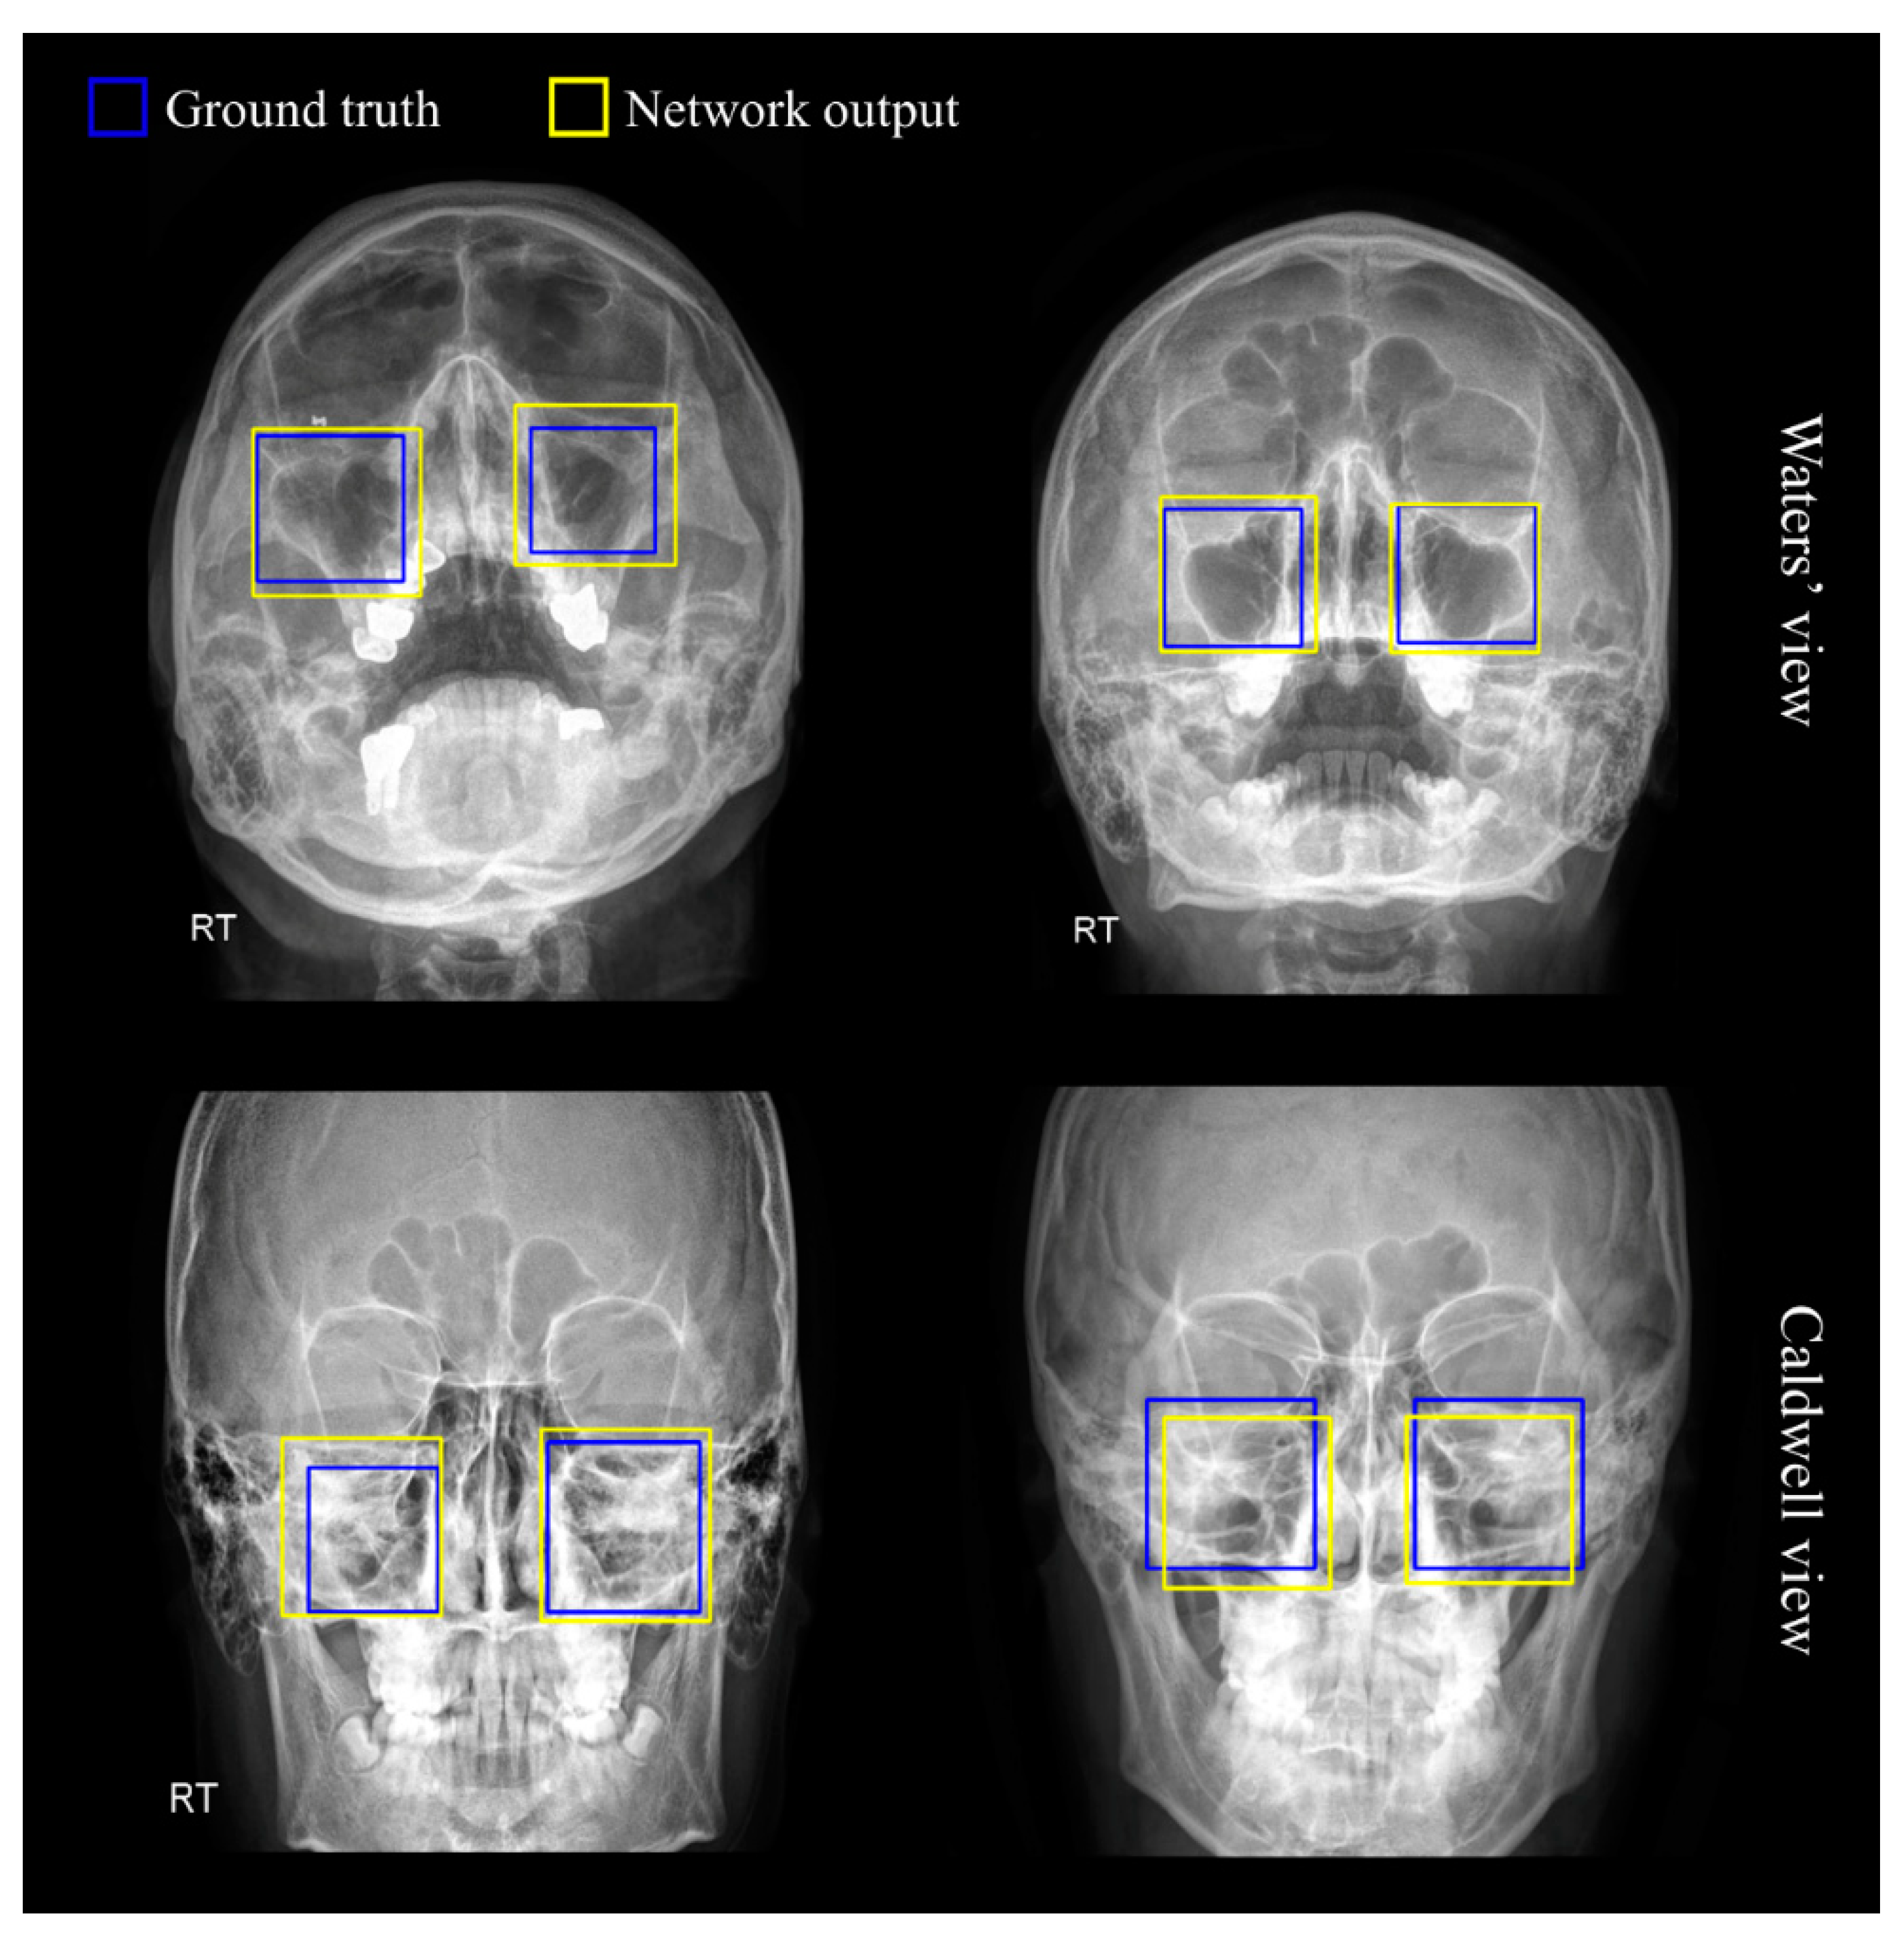

2.5. Region of Sinus Detection

3.1. Region of Sinus Detection